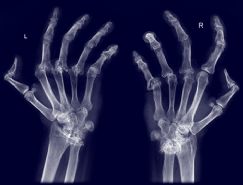

Un test puede ayudar a la terapia contra la artritis reumatoide

Un test desarrollado y patentado por científicos de la ciudad de Ribeirão Preto (São Paulo, Brasil) permite identificar, antes incluso del comienzo del tratamiento, a los portadores de artritis reumatoide que no responden a la droga metotrexato (MTX), considerada el patrón oro en el combate contra la enfermedad.

Datos epidemiológicos indican que el medicamento no funciona en alrededor del 40% de los casos. Actualmente, se hace necesario esperar entre tres y seis meses luego del comienzo de la terapia para descubrir si el paciente está reaccionando. De acuerdo con los médicos, esta demora puede comprometer las posibilidades de cura.

Sin embargo, cuando se rebasa la ventana de oportunidad, un medicamento que podría haber funcionado, de habérselo administrado al comienzo de la inflamación, se vuelve menos eficaz. Asimismo, añadió Louzada Junior, cuanto más tiempo se tarda para controlar el proceso inflamatorio, mayor es la probabilidad de que se produzcan lesiones en las articulaciones.